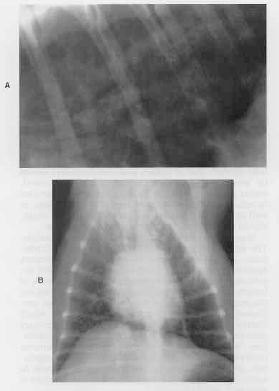

質の高い胸部X線写真は、慢性咳の他の原因を除外するかあるいは肺炎、気管支拡張症および心疾患のような合併疾患を示すのに重要である。閉塞障害のない慢性気管支炎の犬の胸部X線写真は通常気管支壁の肥厚を示すか、あるいは気道に沿った陰影が全体的に強調されているか、もしくはその両方を示す。(図52−1) 気管支壁肥厚は、「ドーナツ」影および「tram lines」(それらはそれぞれ、肥厚した気管支壁の走行に平行または直交する投影から発生する)によってそれぞれ認識される。肺胞浸潤影の存在は同時に肺炎あるいは肺水腫があることを示しているかもしれない。しかしながら、多くの犬が正常と思われる肺野を示す。したがって、正常な胸部X線写真の所見は、慢性気管支炎の診断を除外するべきではない。

図52−1。A 胸部X線ラテラル像における肺葉背側後部の近接像。B 同じ胸部の腹背像。両方の所見は閉塞性障害のない慢性気管支炎の犬からのもので、気管支壁の肥厚、および気道に沿っての間質影の全体的増加を示す。